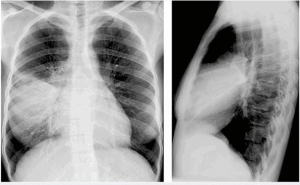

Hình ảnh rõ nét, độ phân giải cao: Cho phép quan sát chi tiết tổn thương nhu mô phổi, các vùng mờ, tổn thương dạng nốt, hang lao…